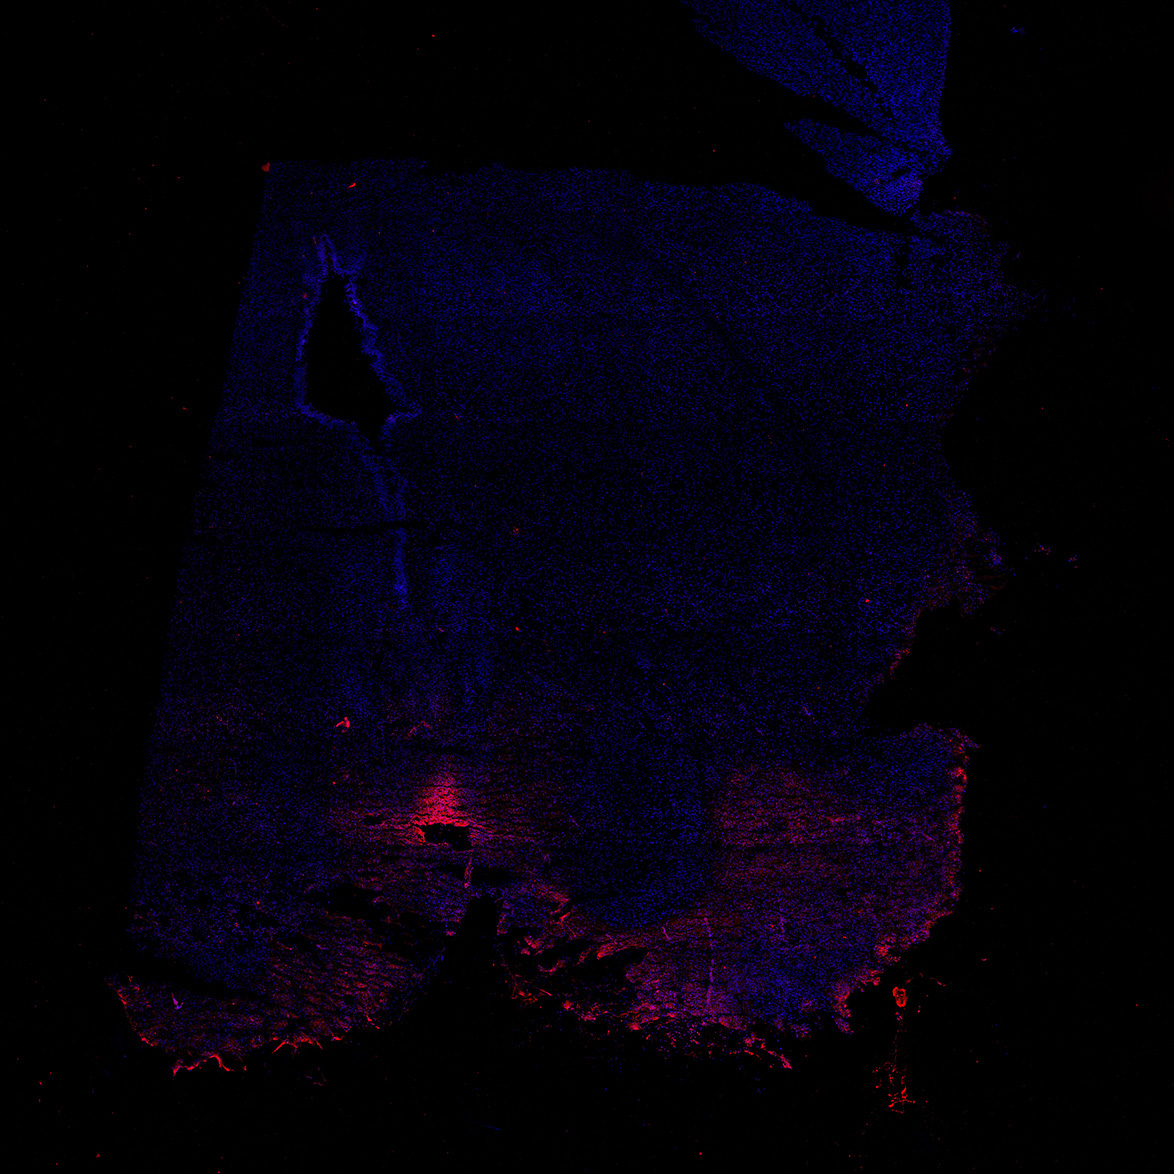

Merged

11PCW human midbrain

DAPI

TH